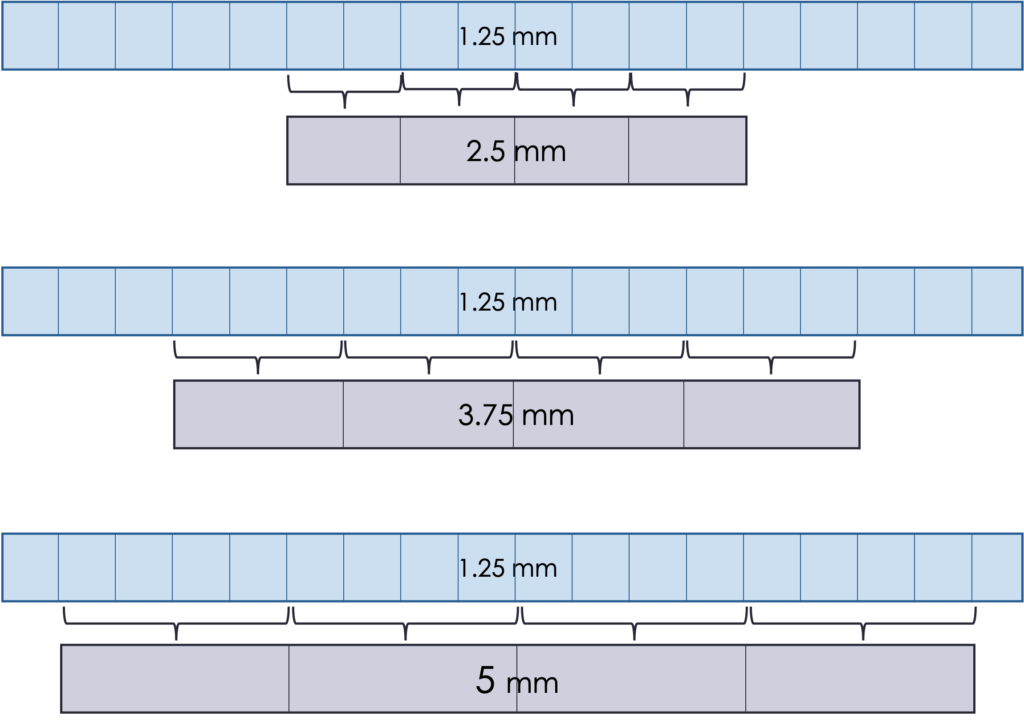

The detector size determines the minimum slice thickness, which is typically 0.5 to 1.25 mm. It is possible to group elements to create thicker slices. This is typically done at the reconstruction stage.

Thicker slices mean better SNR because there is more data in every slice (higher N). However, the spatial resolution is worse because more information is being averaged and fine details become blurred.

Another consequence is that thicker slices can mean a reduced radiation dose. More photons are contributing to each slice, so fewer photons are needed overall to maintain the same SNR. It can also be quicker to acquire, which is important if the patient may have trouble staying still (pediatric, breath hold, trauma, etc.).

It is also quicker to read the slices, or create contours for radiation therapy, if there are fewer slices covering the area of interest. The choice of slice thickness depends on the clinical situation.

An example of the effect of different slice thickness in the abdomen is shown below. The 5 mm slices are less noisy but have worse resolution than 1 mm slice thicknesses. There is usually a “sweet spot” that balances SNR and resolution, but it depends on the clinical task and the anatomy imaged.